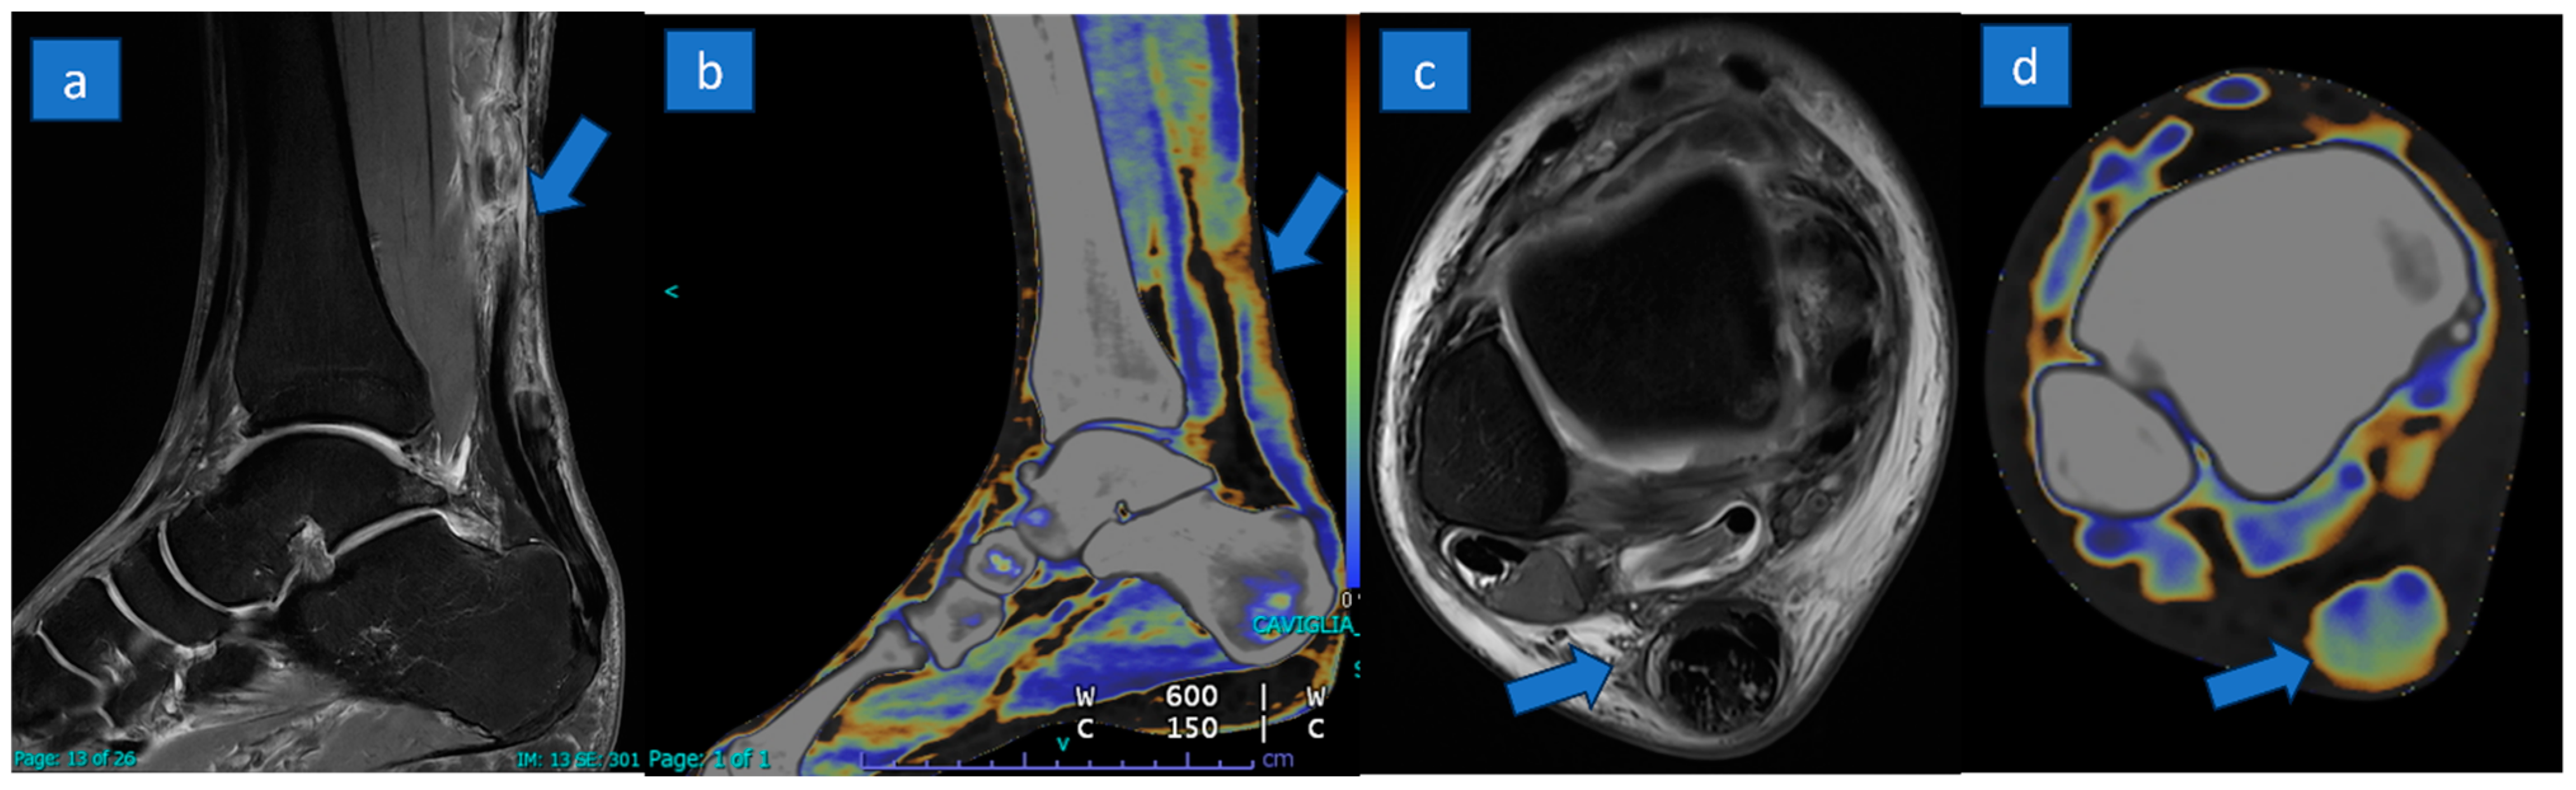

3.2. MRI Results

3.3. DECT Results